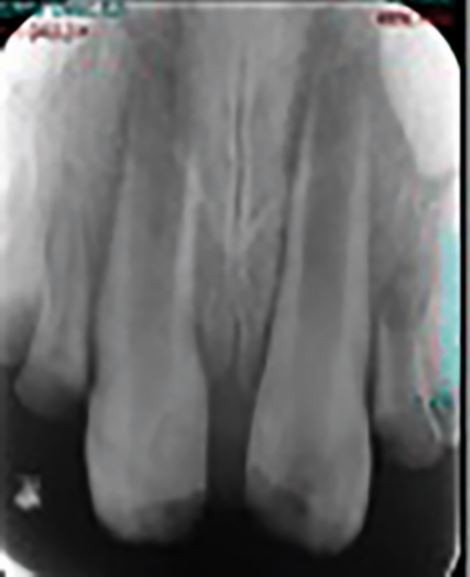

Fig. 4

From: Endodontic implications of dental trauma: useful tips for primary dental care

Teeth that are traumatised and subsequently experience pulpal necrosis and apexogenesis in young children might have very immature roots that are susceptible to fracture. Regenerative endodontic procedures are evolving to provide a possible improved prognosis for these cases in the future